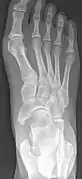

Radiological images

Cornuate navicular bone